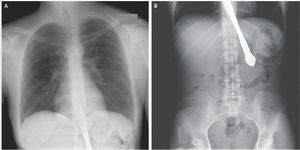

X-ray shows a knife that became stuck in a 30-year-old woman's esophagus and stomach, causing her "chest discomfort," according to a report of her case.The woman had previously had the eating disorder bulimia, and had inserted the knife into the back of her mouth in order to demonstrate that she had lost her gag reflex. But she laughed unexpectedly, and the knife fell into her body, according to Dr. Aida Venado and Dr. Sarah Prebil, of Emory University School of Medicine, who reported the woman's case in the New England Journal of Medicine in 2012.Doctors were able to remove the knife in a procedure called an esophagogastroduodenoscopy, in which a small camera is used to view the esophagus. The woman recovered, and she was able to eat without complications, according to the report.